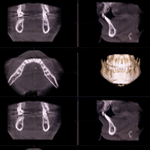

Dental Implants

Restore missing teeth with durable and natural-looking dental implants. Our expert team ensures long-lasting function and aesthetics.

Implant placement typically requires 1–2 hours, followed by a healing period of 3–6 months for osseointegration. Afterward, the custom crown is attached, completing the restoration.